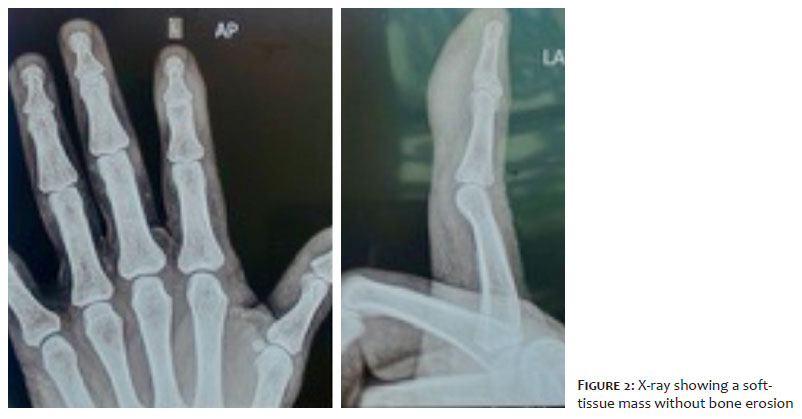

A 52-year-old woman presented to the Dermatology outpatient service with discomfort in her left index finger and an enlarging mass for 3 years. On physical examination, there was a tender nodule 2 × 2 cm on size at the volar aspect of the left index finger involving the distal phalanx (Figure 1). The nodule was ill-defined from the surrounding tissue and not associated with paresthesia. Movement of the distal interphalangeal joint was mildly restricted. The patient had no history of smoking or alcohol abuse. Family history was also not relevant. X-ray imaging showed a soft-tissue mass without bone erosion (Figure 2).